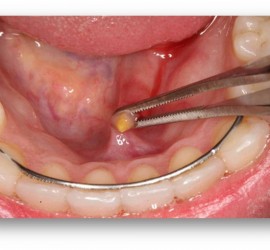

Аденокарцинома — злокачественные эпителиальные опухоли, образующие железистые и папиллярные структуры, но не имеющие характерных признаков других видов рака слюнных желез. Возникают как в больших, так и в малых слюнных железах. Гистологически связаны с протоками слюнных желез. Наиболее характерные морфологические признаки аденокарциномы слюнных желез — пролиферация эпителия в протоковых образованиях в виде […]